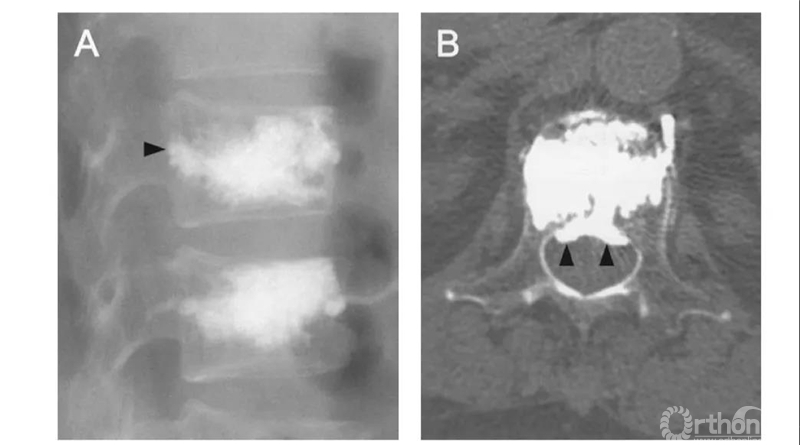

S经节段血管渗漏:沿节段静脉走行弥散。轴位CT呈水平走行。有时会顺着血管上下弥散,矢状面呈垂直或斜行。

C经皮质缺损渗漏:顺着缺损区到处跑,椎体周围、椎管内、椎间盘,哪里有路往哪走。

侧位X片看骨水泥在椎间孔周缘,CT显示渗漏进入椎管,累及椎间孔。